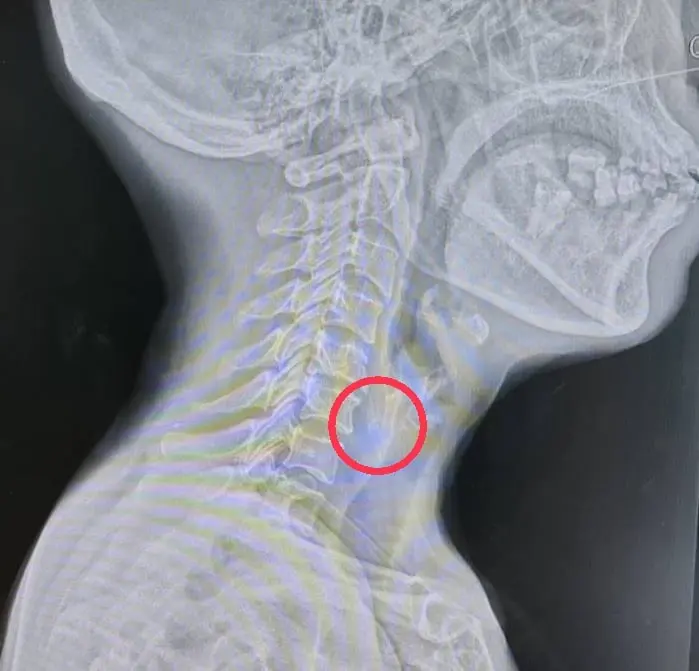

เมื่อผลตรวจโควิดออกมาเป็นลบ จึงเข้าไปส่องดูในคอไม่เห็นอะไร มีเพียงน้ำลายฟูมปาก สั่งเปิดเส้นให้สารน้ำ ประเมินสัญญานชีพ มีความดันสูงเล็กน้อย ชีพจรเร็ว ประเมินอาการปวด ให้ระดับ 10 เต็ม10 อยู่เฉย ๆ ก็ปวด กลืนน้ำลายยิ่งปวดมาก ไม่ค่อยอยากพูดอะไร จึงสั่งให้งดน้ำอาหารทันที และส่งเข้าห้องเอกซเรย์ที่อยู่ติดกัน เอกซเรย์ที่ส่วนลำคอ และส่งภาพเอกซเรย์ผ่านไลน์ปรึกษาแพทย์ผู้เชี่ยวชาญด้านหูคอจมูก ที่อยู่ในห้องผ่าตัด

จากภาพจะเห็นเงาขาว ๆ จาง ๆ 2 ชิ้น อยู่บริเวณลำคอ ระดับเดียวกับกระดูกคอที่ 6 จึงสงสัยว่าน่าจะมีสิ่งแปลกปลอมเป็นเศษกระดูกอะไรสักอย่างที่ผู้ป่วยกินเข้าไปแล้วติดในหลอดอาหาร ส่วนบน